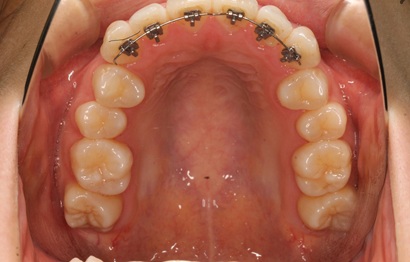

2Dリンガルブラケット

みなさん2Dリンガルブラケットは、歯の凹凸を治すのに有効なリンガルブラケットです。期間も短期間で済むことが多く、通常のリンガルブラケットより費用も抑えられます。以前、半年後の結婚式に間に合うように治療をしてほしいという患者さんの治療をしたこともあります。平べったい形なので違和感も少なく、発音も影響を受けません。興味がある方は、一度お話だけでも聞きにいらしてください。